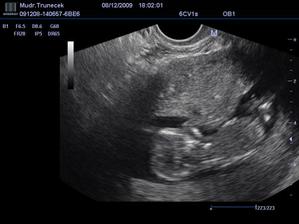

Náš František a jeho mladší sourozenec

Dne 17.10.2009 mamka zjistila, že, ač neplánovaně, budu mít sourozence.TP je zatím 21. 6.2010.